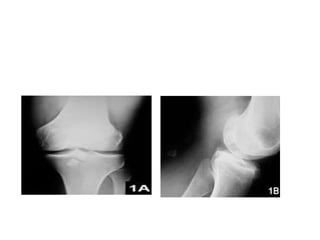

• Larger loose bodies are typically calcified and

thus easily visible on a plain film x-ray of the

affected joint